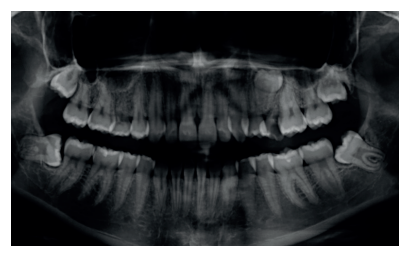

Introducción: La prevalencia de maloclusiones dentales es elevada, según los diversos estudios epidemiológicos realizados. Por ello llevamos a cabo un estudio descriptivo de tipo transversal con 87 modelos de estudio de ortodoncia de estudiantes de la Facultad de Odontología de la Universidad San Pablo-CEU, con el objetivo de determinar la prevalencia de maloclusiones en este colectivo, según la Clasificación de Angle.

Resultados: La distribución de la muestra fue un 77% de mujeres frente a un 23% de hombres. De ellos, el 71,3% habían sido tratados previamente con ortodoncia, el 28,7% no habían recibido tratamientos previos de ortodoncia. Además, el 67,8% pertenecían al grupo Nacional y el 32,2% al Internacional. Tanto la Clase Canina como la Molar más prevalente fue la Clase I, seguida de la Clase II y, por último, la Clase III de Angle.

Conclusiones: Se puede concluir que la Clase I es la oclusión de Angle más prevalente, a la que le siguen la Clase II y, en último lugar, la Clase III.